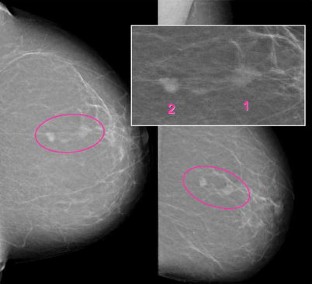

Abb. 1